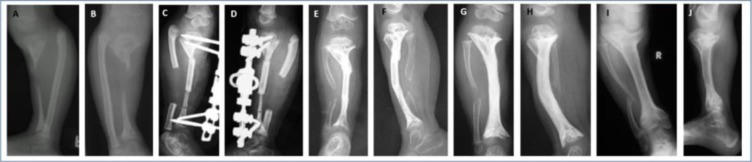

Abstract Image

Background. Post-osteomyelitis bone defects represent a challenging clinical situation. This retrospective cohort study was designed to evaluate the long-term outcome of the use of non-vascularized bone grafts in the management of such defects in children. Methods. Twenty-three children (mean age 7 years, range 2-13 years) were studied. All of the defects were segmental (mean defect length 6 cm, range 3-12 cm), involving the tibia, femur, humerus and radius. Fifteen children presented with an active infection and were managed with a staged protocol. The first stage included sequestrectomy or debridement of the site. The second stage, i.e. the graft procedure, was performed after 12 weeks on average. The mean follow-up was 9.2 years (range 7-15 years). Results. Bone union was primarily achieved in 14 children (61 %). Complications were experienced in the remaining nine children. Conservative and surgical treatment led to bone union in all patients within 5 years of the index procedure. Recurrence of infection was observed in two patients (8.7 %). All of the children were able to use the limb at the final follow-up; only three required the use of a brace. Conclusions. Autogenous non-vascularized bone graft may be considered a valid option in the treatment of bone defects secondary to osteomyelitis in children.